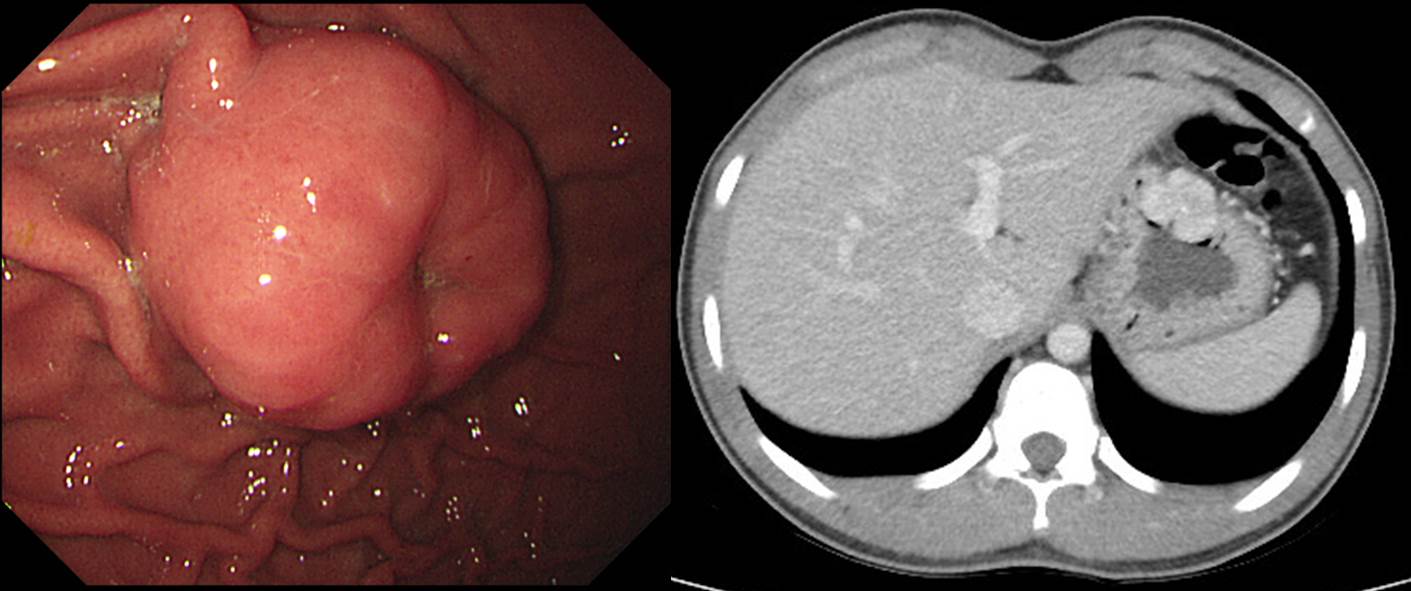

ºù»êÀÇ Àϰ¢°ú °°Àº SMT. Wedge resection: GIST. 4x3cm mitosis 3/50 HPF

°ËÁø UGI ¿¡¼­ ¹ß°ßµÈ SMT·Î ¼ö¼úÀ» ½ÃÇàÇÔ.

Stomach, wedge resection: Leiomyoma (6x3 cm)

C-KIT (CD 117) : Negative in tumor cells

Actin (Smooth muscle) : Positive in tumor cells

ÀÌ Á¤µµ¸é Ãß°¡ °Ë»ç°í ¹¹°í ¾Æ¹« °Íµµ ÇÊ¿äÇÏÁö ¾Ê½À´Ï´Ù. ¹Ù·Î ¼ö¼ú. Àú´Â ÀÌ·± °æ¿ì EUS °Ë»ç¸¦ ÇÏÁö ¾Ê½À´Ï´Ù. Çϳª ¸¶³ª ¼ö¼úÀ» ÇØ¾ß Çϰí Ä¡·á °èȹÀÌ ¹Ù²îÁö ¾ÊÀ¸´Ï±î.

Stomach, "GIST", wedge resection:

Gastrointestinal stromal tumor of intermediate risk of malignant potential by proposed modification for adjuvant therapy (2008) (see note);

1) tumor size: 4.2x4.2x4 cm

2) mitosis: 7/50 HPF (high powered fields)

3) histological type: spindle

4) necrosis: absent

5) cellularity: intermediate

6) cellular atypia: mild

7) invasion into mucosa: present

8) resection margin involvement: absent

Note: Intermediate risk by NIH (2002) and moderate risk (16%) of progressive disease by Miettinen (2006).

. Ki-67 : Positive in about 7% of tumor cells

. PHH3 : Positive in tumor cells (up to 1/50 HPF)

. PKC: Positive in tumor cells

. DOG-1 : Positive in tumor cells

. C-KIT (CD 117) : Weak positive in tumor cells